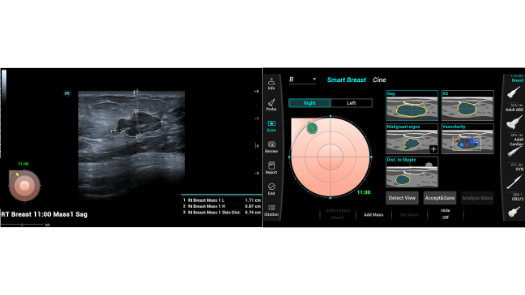

Bez wzgl?du na to, czy pracujesz w szpitalu, przychodni, czy u?ywasz ultrasonografu do badaÅ ogÃģlnych, w opiece zdrowotnej kobiet lub w badaniach sercowo-naczyniowych, w serii Consona znajdziesz bardzo pot??ne narz?dzia, aby utrzyma? si? w czo?Ãģwce.

Galeria obrazÃģw